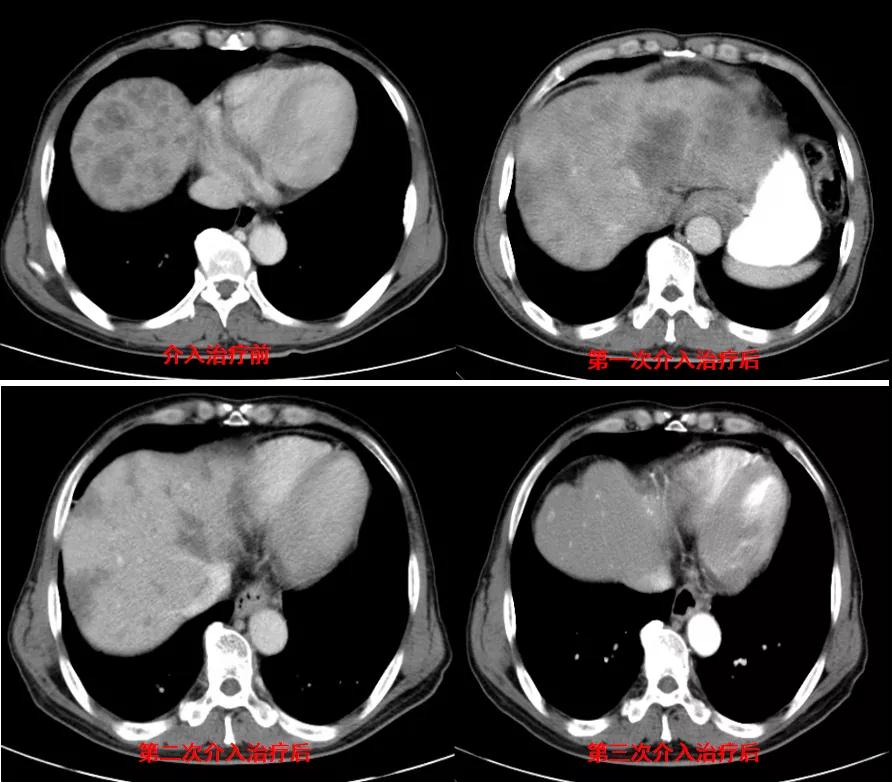

诊治经过:2020年12月16日患者行第二次经皮动脉化疗灌注栓塞术(铂类+氟尿嘧啶)治疗,并继续联合吡咯替尼治疗。结果见图3。

图3

诊治经过:2021年5月16日患者行第三次经皮动脉化疗灌注栓塞术(铂类+氟尿嘧啶)治疗,并继续联合吡咯替尼治疗。结果见图4。

图4